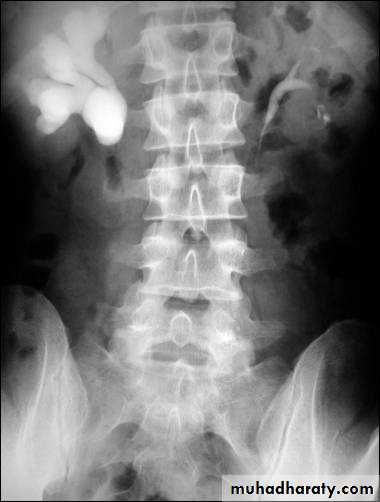

High density renal stonesStage horn calculus KUB filmsradio opaque stones